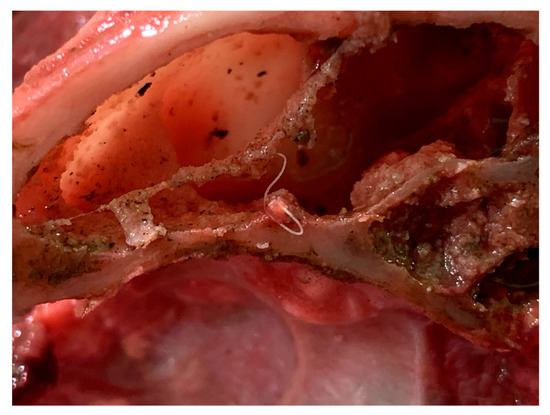

2.4. Necroscopic Examination and Histopathology